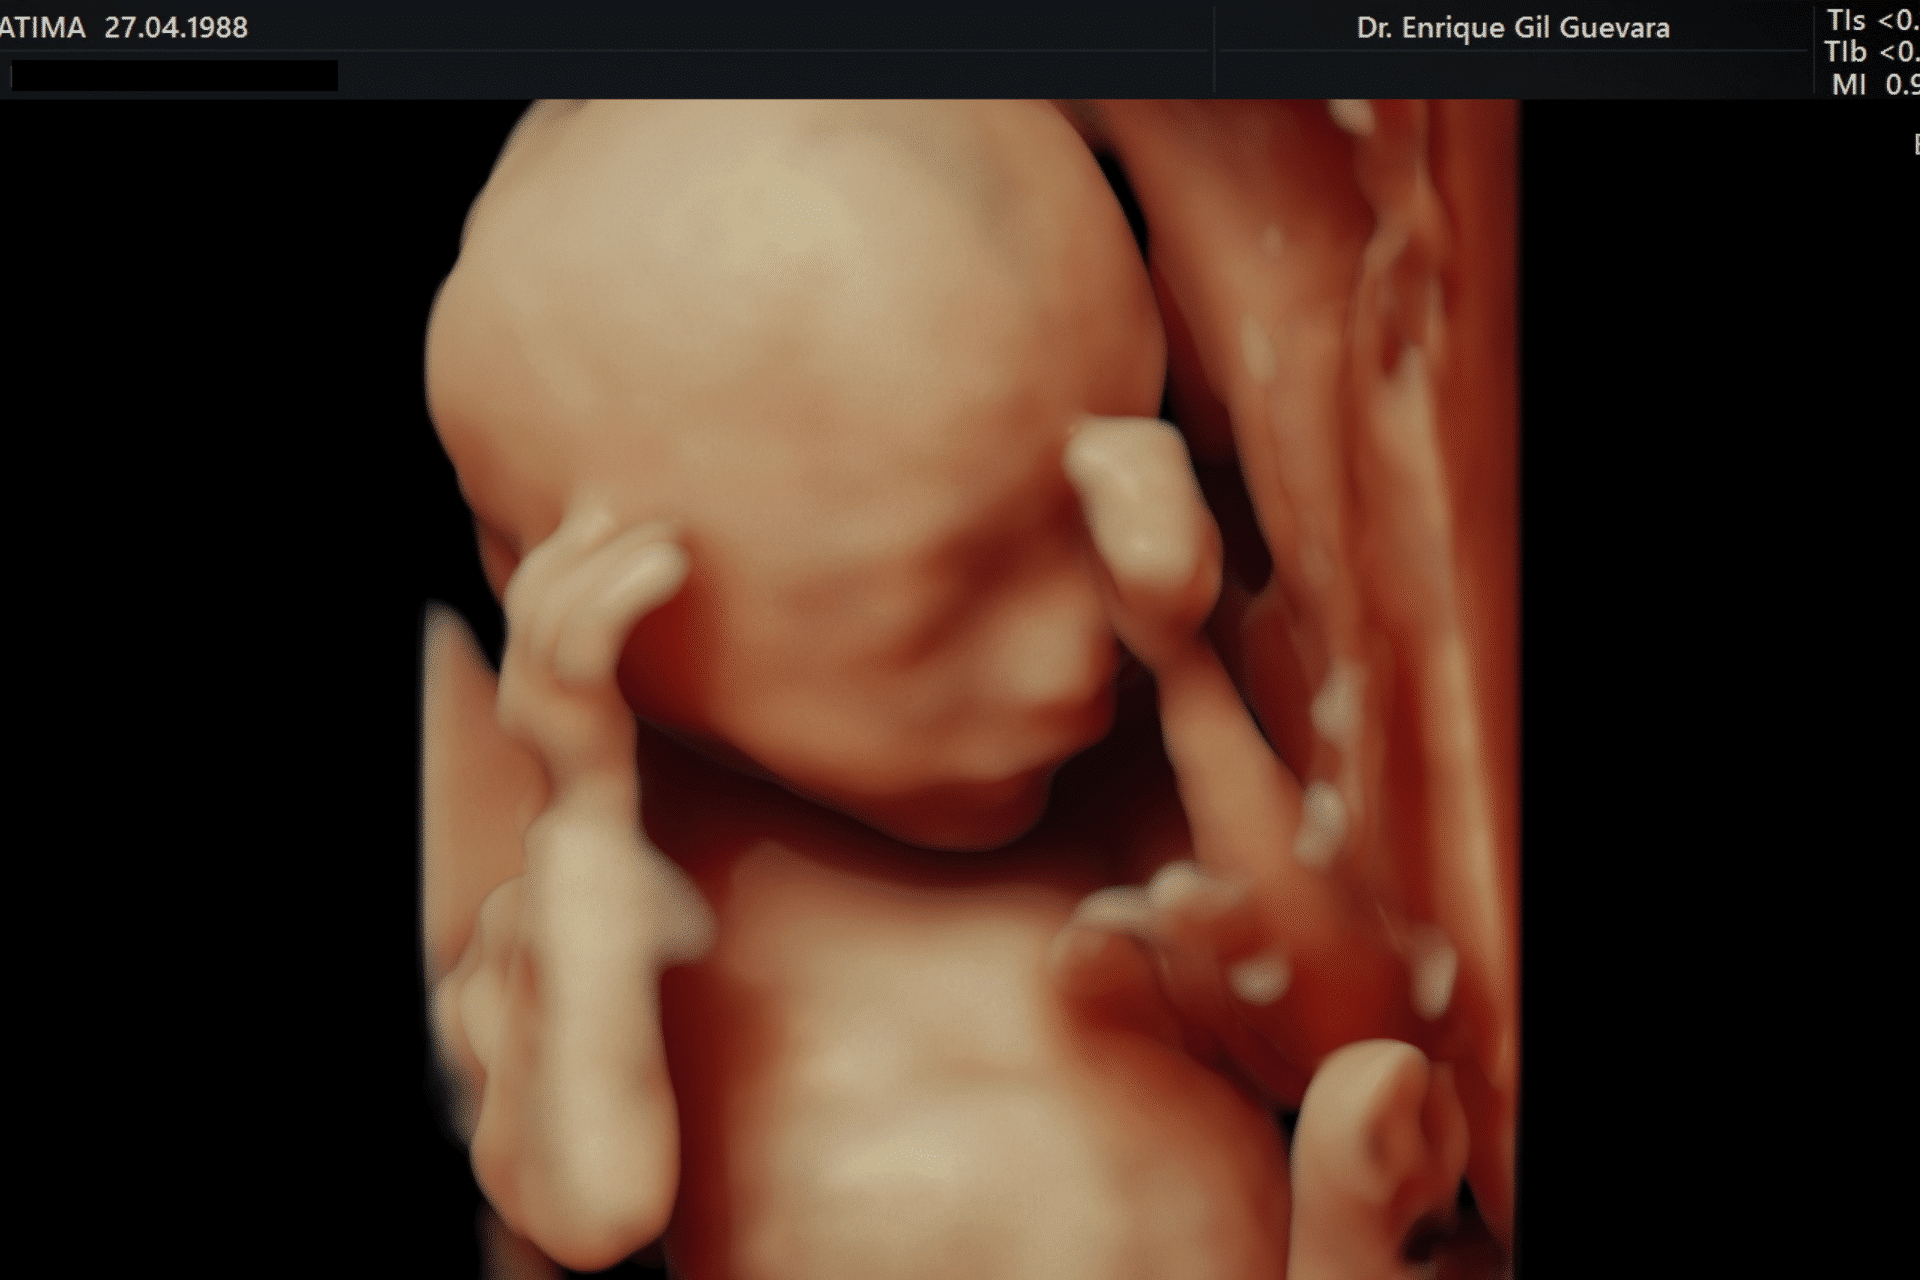

La ecografía genética es un examen que evalúa el desarrollo del bebé durante el embarazo.

Este procedimiento se realiza utilizando tecnología avanzada de ultrasonido para obtener imágenes precisas del feto y analizar aspectos específicos de su formación.

A través de este estudio, se pueden detectar condiciones genéticas y estructurales que podrían influir en la salud del bebé, permitiendo un seguimiento detallado desde las primeras semanas de gestación.

- Utilizar un transductor que emite y recibe ondas sonoras para generar imágenes detalladas del bebé en tiempo real.

- Interpretar las imágenes por parte de un especialista en ultrasonografía, quien analizará aspectos específicos como la estructura anatómica, el crecimiento y la presencia de posibles anomalías.